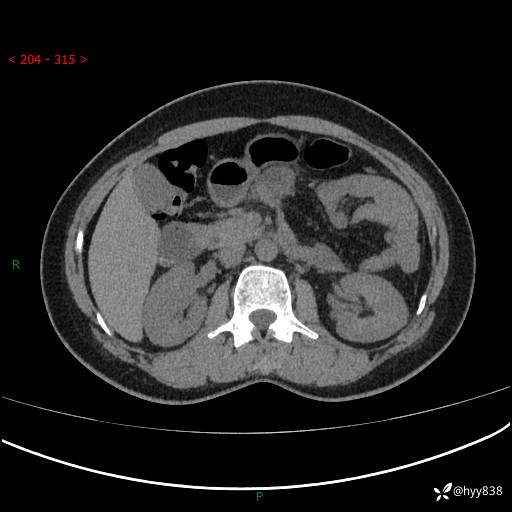

51岁/女,腹痛腹胀1天。白班偶遇,收藏教学备用---(公布详细手术过程)

现病史:患者1天前无明显诱因下出现左上腹部及腰背部胀痛不适,阵发性加剧,伴肛门停止排气;无发热,无恶心呕吐,无畏寒发热,无心慌气短等不适,于当地市第二人民医院就诊,行腹部ct检查提示左上腹区肠系膜血管从剧聚集,分布紊乱伴肠管局限性稍扩张积液,不完全性肠梗阻;考虑子宫颈纳氏囊肿,双侧附件区囊状灶;予以抗炎及对症支持等治疗后未见明显缓解,现患者为求进一步治疗来我院急诊就诊,遂以“肠梗阻”收住入院。 病来,神志清,精神可,饮食睡眠不佳,经灌肠后排便2次,小便正常,体力体重无明显变化。

上腹部CT平扫